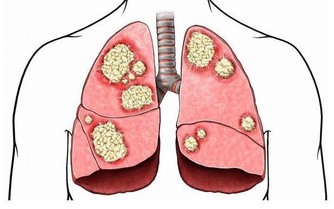

2、門靜脈高壓

表現為食道靜脈曲張,脾大和腹水,尤以食道靜脈曲張最危險。由於曲張靜脈的血管壁薄,很易破裂導致消化道大出血。